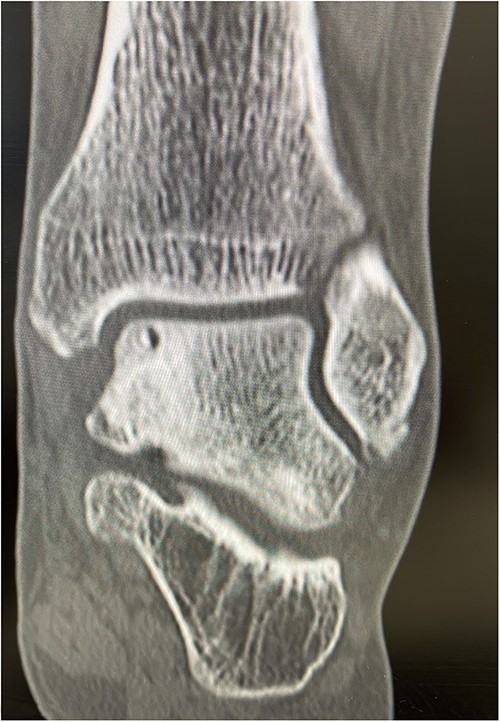

An X-ray of the ankle showed a radiolucency at the anteromedial aspect of the talus, suggesting a subchondral cyst. This lesion measured 18 × 18 × 11 mm on the CT scan in the medial patellar dome with a focal vacuum at the medial talocrural joint. The overlying cortex was thinned out with medial focal cortical defect. There was no collapse of the articular surface (Fig. 1).